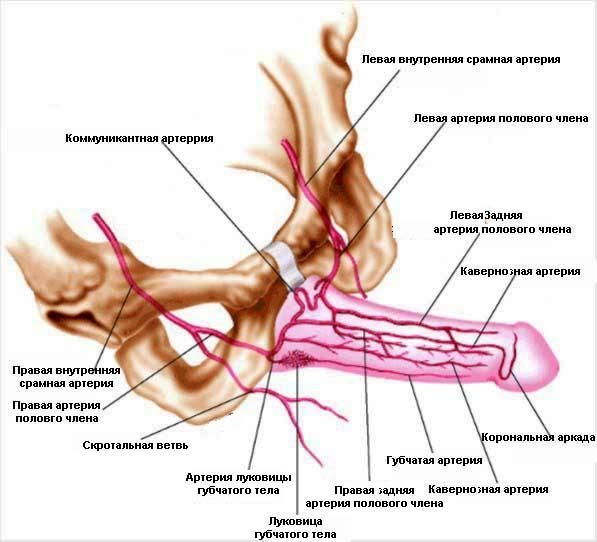

После физической и психоэмоциональной стимуляции нервы посылают сигнал к СОСУДИСТОЙ системе, что значительно увеличивает приток крови к половому члену. Две артерии несут кровь в кавернозные тела полового члена и после кровенаполнения и увеличения давления в кавернозных телах полового члена происходит эрекция.

В 80% случаев причина носит СОСУДИСТЫЙ характер. Как было объяснено выше, в случае нарушения притока крови к половому члену, НАСТУПАЕТ ЭРЕКТИЛЬНАЯ ДИСФУНКЦИЯ. Основной причиной снижения притока крови служит сужение просвета приводящих артерии в результате атеросклеротического процесса в стенке артерии.

Если причиной эректильной дисфункции является недостаточный приток крови по артериям в половой член, то диагноз ставиться на основании специального исследования этих артерии – АНГИОГРАФИИ. В случае наличия сужений или закупорок в приводящих артериях, они четко видны на ангиограммах.